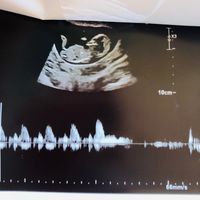

Ciaooo qualcuna ha sentito parlare del metodo Ramzi? A voi ci ha azzeccato o ha sbagliato? Vi metto una foto dell’eco interna a 7+3 “dovrebbe” essere maschio secondo la teoria o sbaglio io a vedere?...

Qualcuna che se ne intende? Io di angoli non ho capito nulla provate a indovinare , forse il 23 agosto riuscirò a vedere il sesso e vi dirò se avete indovinato!!! !